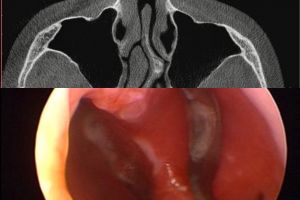

Во втором случае перфорация развилась после спортивных травм носа. Была маленькой и проявлялась свистом, сухостью и образованием корочек. 2 года назад в другом городе проведена попытка закрытия перфорация, после чего она увеличилась. Фото 3.